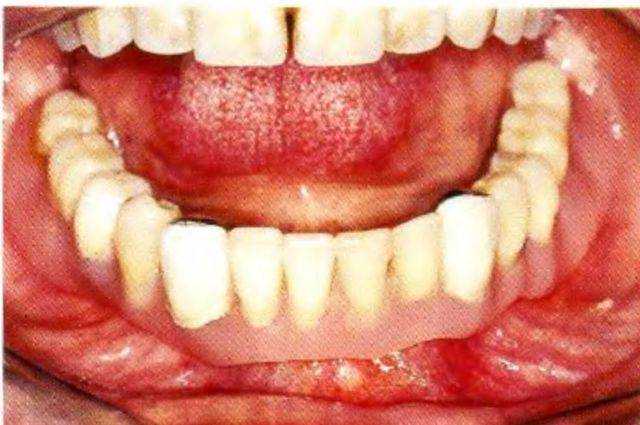

При осмотре определили выраженную атрофию альвеолярных гребней верхней и нижней челюсти, а также сниженную саливацию. Съемные протезы были несостоятельны (рис. 1 -9с). В связи с анамнезом и данными осмотра возникло несколько вопросов:.

Рис. 1-9с. Плохоприпасованная пара съемных полных протезов